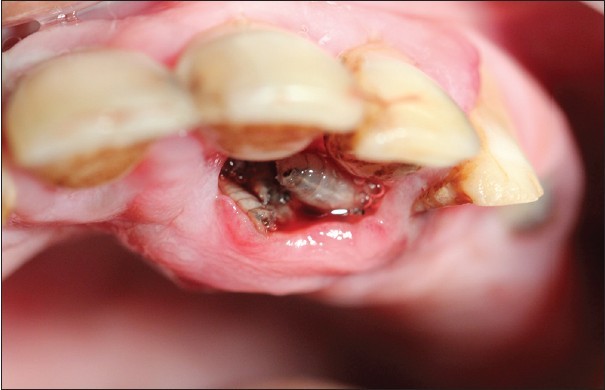

What is Oral Myiasis?

‘Oral’ means something related to the mouth, and it can be related to teeth, gums, tongue, and maxillary Sinus.

Maxillary Sinus is crucial in dentistry; it is located inside the skin in the facial bone below the eyes and front of the ear, and it’s an air cavity lined by cells.

It transfers infection from teeth and oral cavity towards the brain, nose, and vice versa. Sinuses have close relations with the upper 2nd Molars of each side.

‘Myiasis’- It has 2 Greek words, ‘Myia’ means fly insects that fly and ‘as is’ means disease. Flies hatch their larvae (their eggs) on the dead tissue. The larva eats the dead tissue and gets it’s nourishment from it and turns into an adult insect and flies away.

So, Oral Myiasis is a rare disease caused by the Larvae of dipterans. It is reported mostly in developing countries. Myiasis can occur in various parts of our body, not only in the oral region. It can be in the skin, nose, ear, eyes.

What Are The Causes Of Oral Myiasis?

It is caused by flies of order Dipterans, as previously said. Sarcophagidae, Calliphoridae, Oestridae, and Muscidae are genera from the order Dipterans.

Those were some examples of genera. Mostly, it is Chrysomya bezziana (Old Screwworm or Screwworm). It is an obligate parasite; it needs some dead tissue for its species survival, propagation, and reproduction. Its female lays eggs in open wounds, ulcers, scratches, or mucous membranes.

Suppose any injury or cut occurs and remains in direct contact with the air and external environment or not banded properly in its treatment. In that case, it serves as an open wound. Ulcers happen when stomach acid damages the lining of the digestive tract. The mucous membrane is the skin and gingival of the mouth.

Treatment Of Oral Myiasis:

We highly recommend you take the patient to a concerned dental surgeon for treatment as soon as you observe symptoms. It will be good if treatment is done early to contain its infection.

However, the treatment is the surgical removal of larvae. And the result of the activities of larvae is treated after its removal. Turpentine solution help in the extraction of maggots.